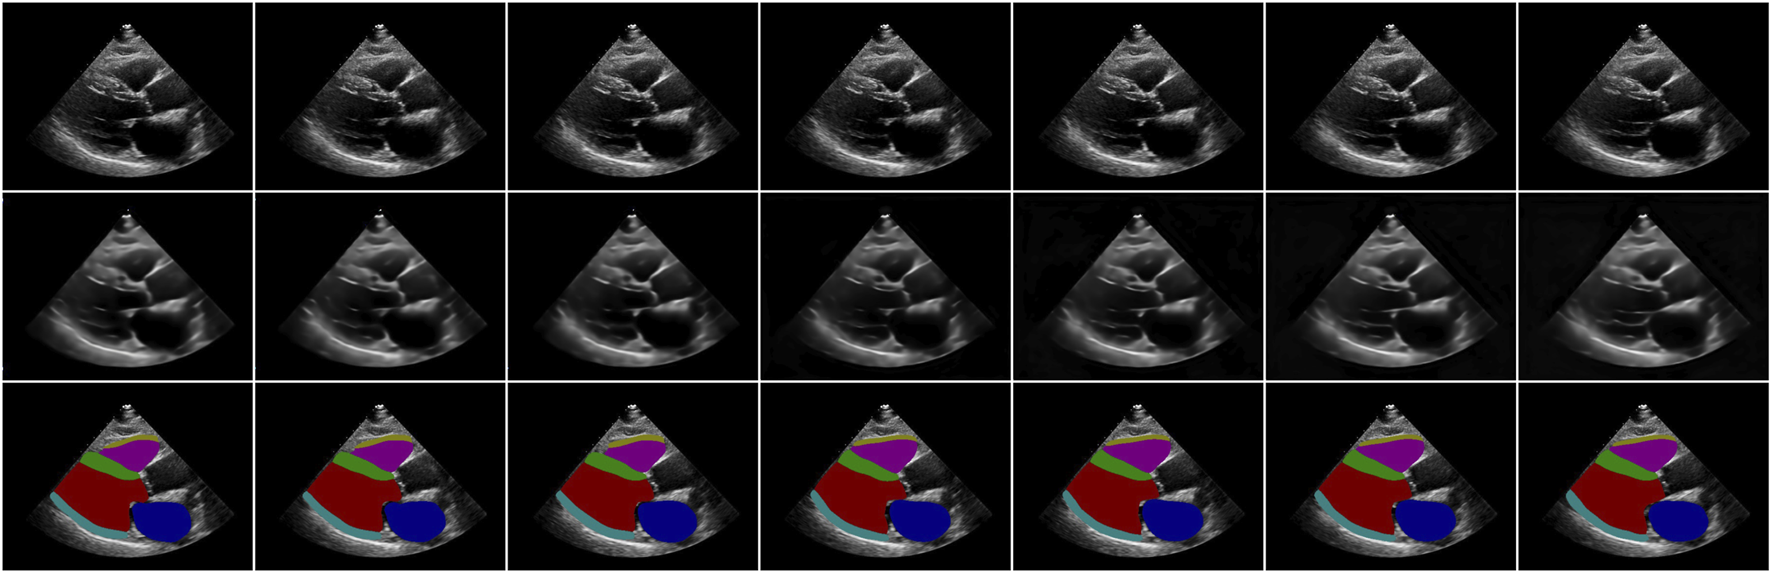

Figure 2 shows an example of video reconstruction and segmentation by Echo-ODE. It is a single run with video interpolation. As we can see, the textures of the original images are reconstructed perfectly except for the noise, and they are more likely to be the smoothed images. This is within our expectation because there are no skip connections from the encoder path and some details are missing. Since the images are reconstructed directly from the NODE, we can draw a tentative conclusion that the NODE model is largely capable of learning certain dynamic characteristics of the video and that NODE is a reliable method to model the dynamics of the heart.

FIGURE 2

Examples of video reconstruction and segmentation by Echo-ODE. Top row: original images. Middle row: reconstructed images. Bottom row: segmentation masks.